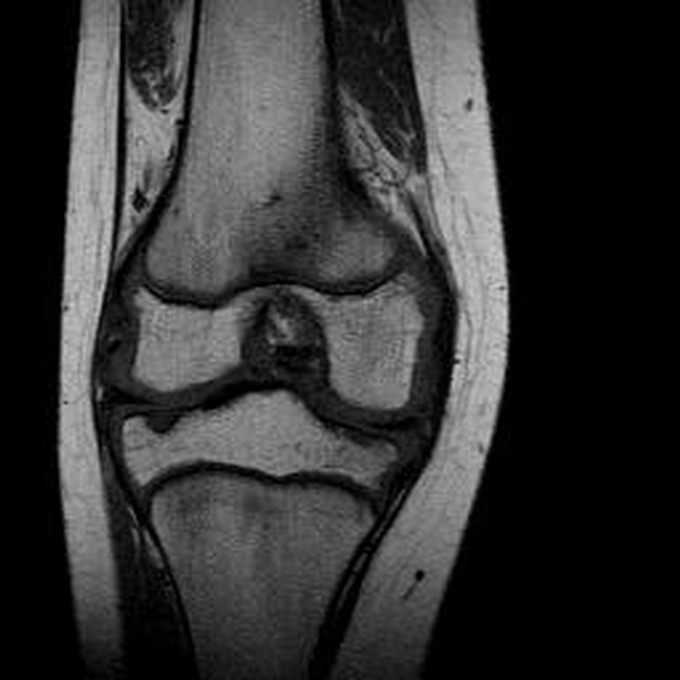

Haemophiliearthropathie bei Haemophilie A.

Arthropathia ARC123 Haemophiliearthropathie bei Haemophilie A.

MRT (high)